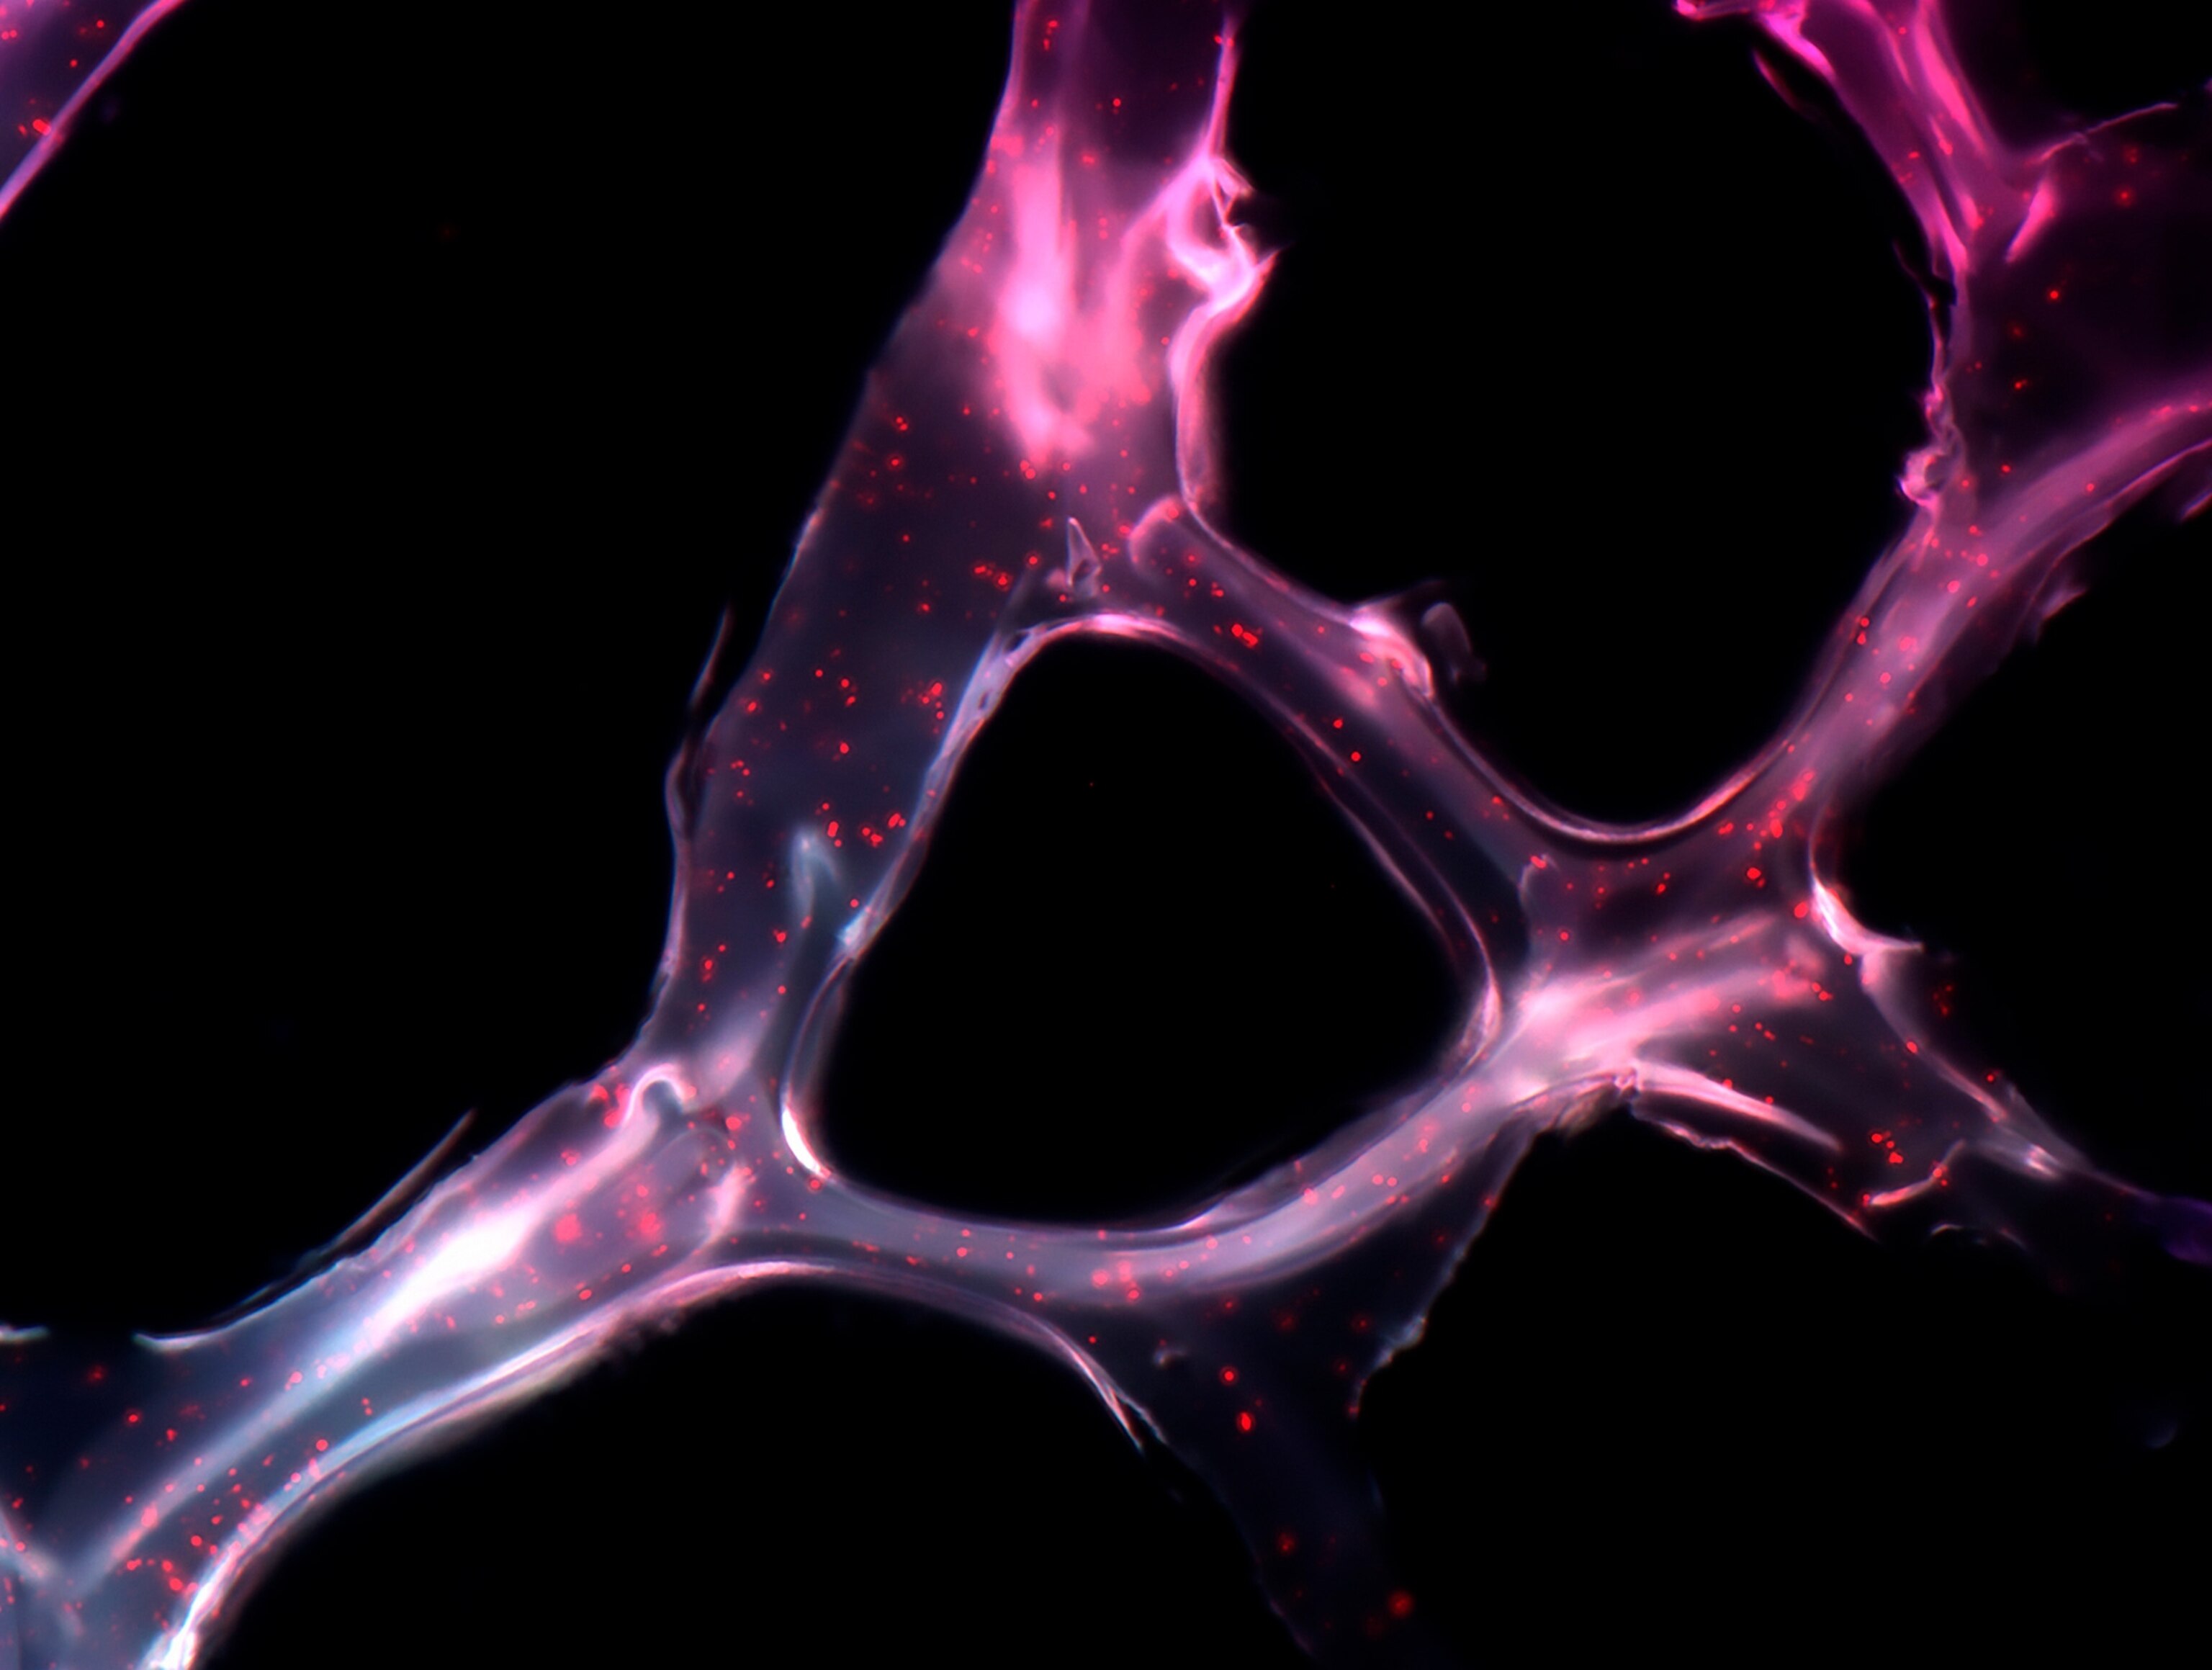

This year's submissions included mediums such as photography, illustrations, super-resolution microscopy, and medical scans.

Nine judges selected a total of 22 images to recognize for their achievements in creating imagery that displays scientific ideas as art. Wellcome Images also partnered with the Koch Institute for Integrative Cancer Research to share and source their pool of submissions.